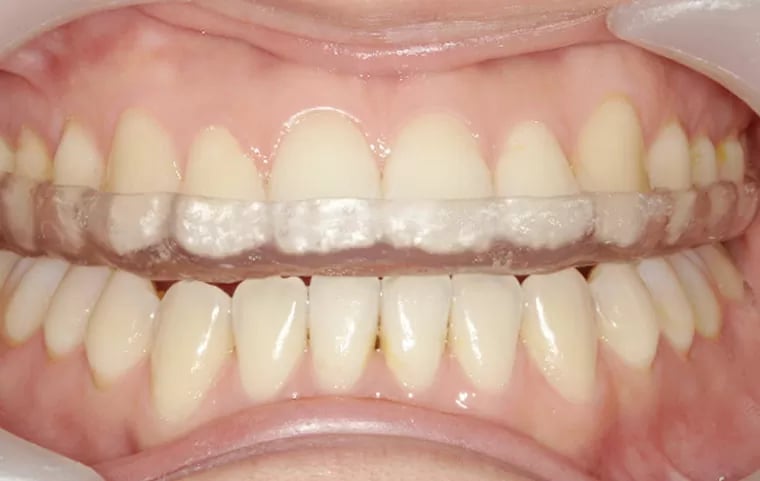

Se utilizan dispositivos que se colocan en la boca para estabilizar la mandíbula y aliviar el dolor y la disfunción.

Colocación de férulas oclusales